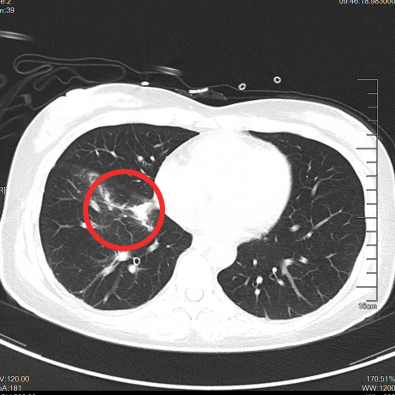

于是

我们给这位年轻患者口服了靶向药

短短一个月

患者肺部和脑部肿瘤就出现明显退缩

随访至今

肺部、颅内、可见淋巴结、腹腔等

多处病灶完全缓解

患者日常生活无异于常人

我们对她能生存5年,甚至10年充满信心

可能更长

……

▲治疗前

▲治疗后1月

▲治疗后2年半